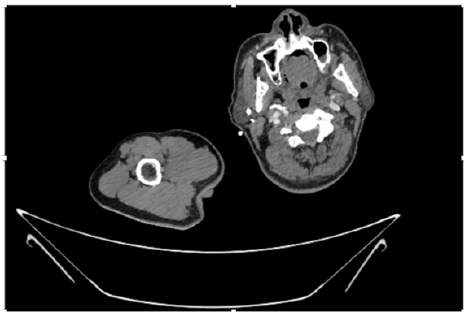

55-years-old chronic smoker had acute, severe pain in the right upper limb for one week; it was cold upto mid arm with skin discoloration. He also noticed numbness and weakness of movement of elbow joint. He underwent below elbow amputation in February 2023 for acute ischemia of left upper limb. He was a current chronic smoker; 15 pack year. General condition was weak; temperature was normal; blood pressure was 100/60mmHg; heart rate was 92/minutes with sinus rhythm; SpO2 was 97% on air; heart was normal. In lower extremities, all peripheral pulses were intact. Local Examination of right upper limb revealed as follows: tenderness; coldness; discoloration; decreased motor function and sensory modalities. Axillary, brachial and radial pulses were not palpable. Hand-held Doppler failed to detect any signal in arterial system; therefore, we arranged for emergency embolectomy. complete occlusion of right upper limb arterial system Full blood count showed high hemoglobin (14.6gm%); normal total WBC and platelet count. Coagulation profile was normal. Parenteral unfractionated heparin, antibiotics, tramadol, proton-pump inhibitors, anti-platelets and HMG CoA reductase inhibitors were given. Doppler ultrasound demonstrated complete occlusion of right upper limb arterial system. CT Angiogram illustrated occlusion of subclavian artery downwards on both sides. Figures 1-14 shows complete occlusion of right subclavian artery without collaterals. On Day ‘2’ of admission, the patient passed black tarry stool for 3 times. However, the vital signs were stable; blood pressure was 100/60mmHg; heart rate was 92/min; SpO2 was 97% on air; the abdomen was soft and not tender. Above elbow amputation was done on Day ‘2’ of admission. Intra-operative findings were as follows: (1) no active bleeding at brachial artery; (2) thrombosis along brachial artery; (3) muscle color and consistency were not healthy.

Figure 10: CT Angiogram at upper arm showing totally occluded right axillary artery; normal internal carotid artery and external carotid artery.